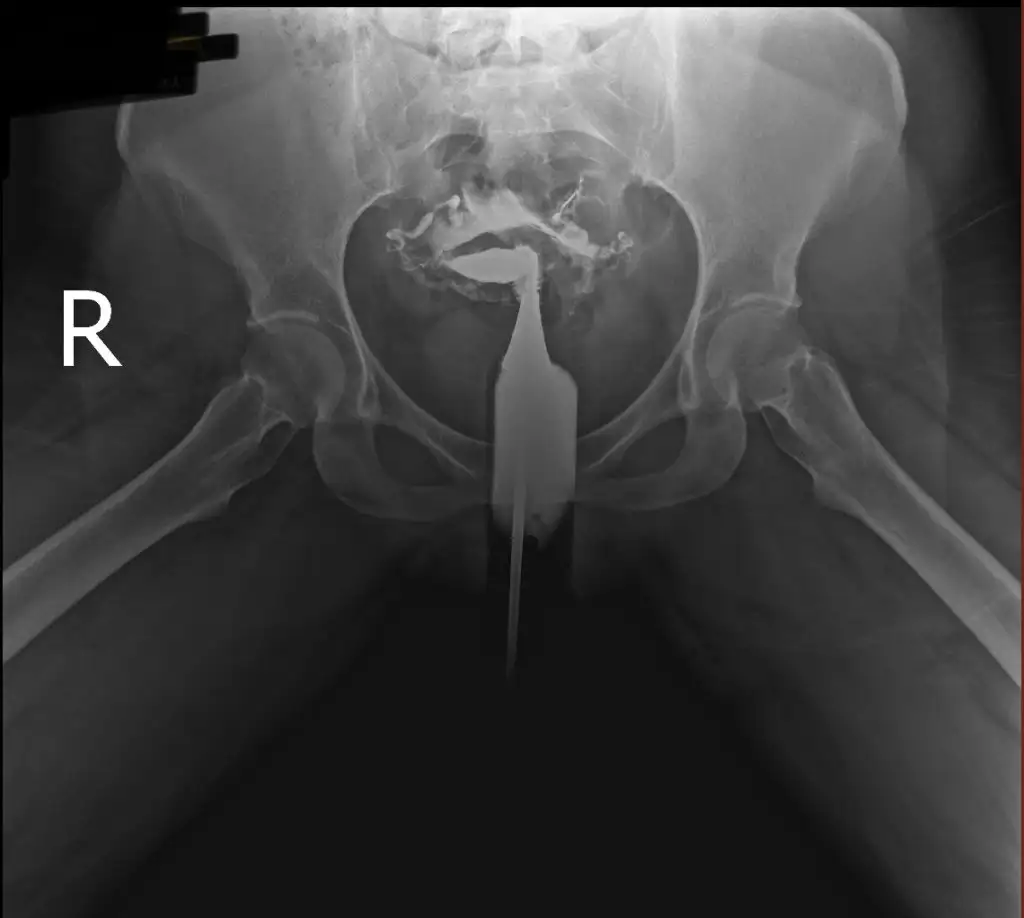

İlaç karın boşluğuna yayılmış tüplerin açık olduğu anlamına geliyor. Farklı bi görüntü var mı tek taraflı gibi duruyor gibi geldi banaHerkese merhaba bana da yardımcı olursanız çok sevinirim. Dün hsg çektirdim doktorum tüplerimin açık olduğunu söyledi. Fakat ben görüntülerden bir şey anlamadım. Bilgisi olan yorumlarsa çok sevinirim görüntüleri yüklüyorum.

Sadece bu görüntüleri yüklemişlerdi e nabıza maalesef teşekkür ederim cevabınız için şüpheye düştüm görüntüden anlamayıncaİlaç karın boşluğuna yayılmış tüplerin açık olduğu anlamına geliyor. Farklı bi görüntü var mı tek taraflı gibi duruyor gibi geldi bana

Açık dedi doktor raporda da açık yazıyordu. Benim de görüntüm böyleydi karın boşluğuna ilaç yayılmış şekildePeki sizin tüpleriniz açık mı çıktı acaba benim görüntülerden bir şey anladınız mı

Anladım teşekkür ederim bende rapor olmayınca kafam karışmıştıAçık dedi doktor raporda da açık yazıyordu. Benim de görüntüm böyleydi karın boşluğuna ilaç yayılmış şekilde

Normal görünüyor rapora göreMerhaba kızlar film sonucum bu. Bilenler bakabilir mi?